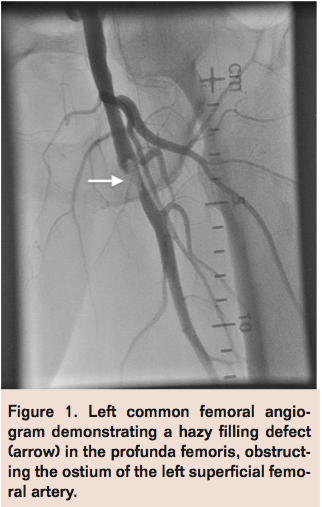

A 4 x 20 mm Sterling Balloon Dilatation Catheter (Boston Scientific) was then inflated distal to the thrombus in the PF and retrieved along with the guiding catheter to trap any embolic material between the balloon and the guide (Figure 2). Finally, the AngioJet catheter (Bayer HealthCare Radiology & Interventional) was advanced over the V-18 wire into the PF and SFA for rheolytic thrombectomy (Figure 3). Subsequent angiogram revealed moderate improvement in flow with persistent thrombotic material in both PF and SFA. A 6 x 100 mm Sterling Balloon Dilatation Catheter and a 4 x 30 mm Sterling Balloon Dilatation Catheter were then used to perform simultaneous kissing angioplasty of the SFA and PF respectively with good expansion (Figure 4). Final angiogram revealed significant improvement in flow through the SFA and PF segments with minimal residual thrombotic debris that were non-flow limiting (Figure 5). The patient was noted to have clinical reperfusion of his left lower extremity with resolution of symptoms, and he was discharged on hospital day 17 with a 6-week course of intravenous antibiotics.